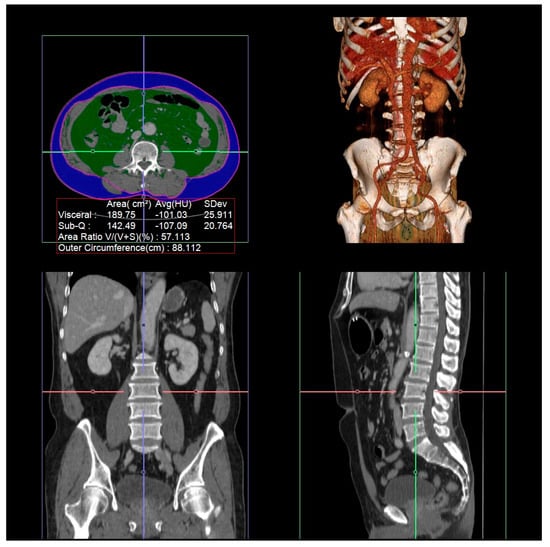

2.2. Measurement of Visceral Fat Area, Subcutaneous Fat Area, and Total Abdominal Muscle Area